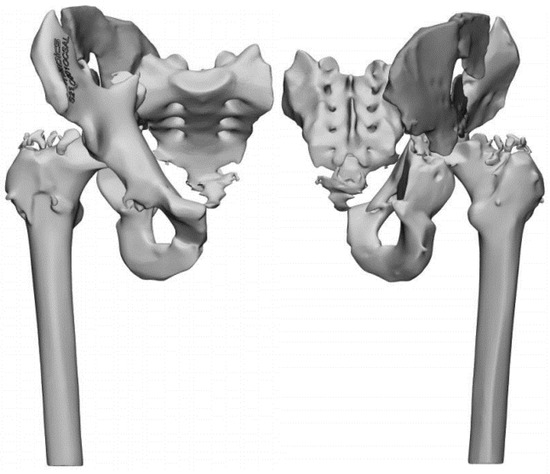

2. Case Report